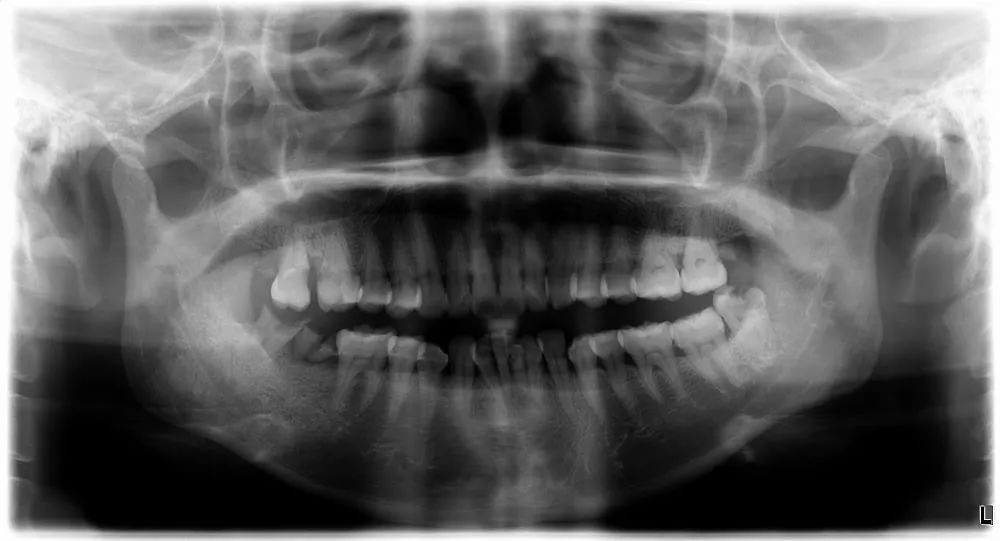

口腔曲面体层片也叫口腔全景片,一次曝光即可获得全口牙齿、上下颌骨、鼻腔、上颌窦及颞下颌关节等部位的影像。应用于颌骨多发病变、范围较大的颌骨病变、双侧颌骨的对比及原因不明症状的检查,广泛应用于口腔颌面部的大多数影像学检查。

儿童常用的根尖片、全景片辐射小,偶尔拍片对身体无害,家长不必过于紧张。